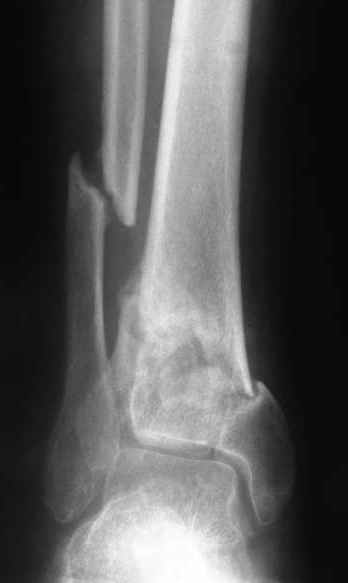

A 56 year old laborer fell off a wall approximately 5 months ago. He sustained an open pilon fracture. He was treated with debridement and external fixation. After he was treated for 4 months, the external fixator was removed.

The patient had no medical insurance and was therefore transferred to my care by his treating surgeon. He has remained NWB. He denies pain in his ankle. He has painless dorsiflexion and plantarflexion of his ankle joint.

I have attached his x-rays. I have also attached an WMV movie file of his axial CT (if you are unable to view this, I can post an MPEG file).